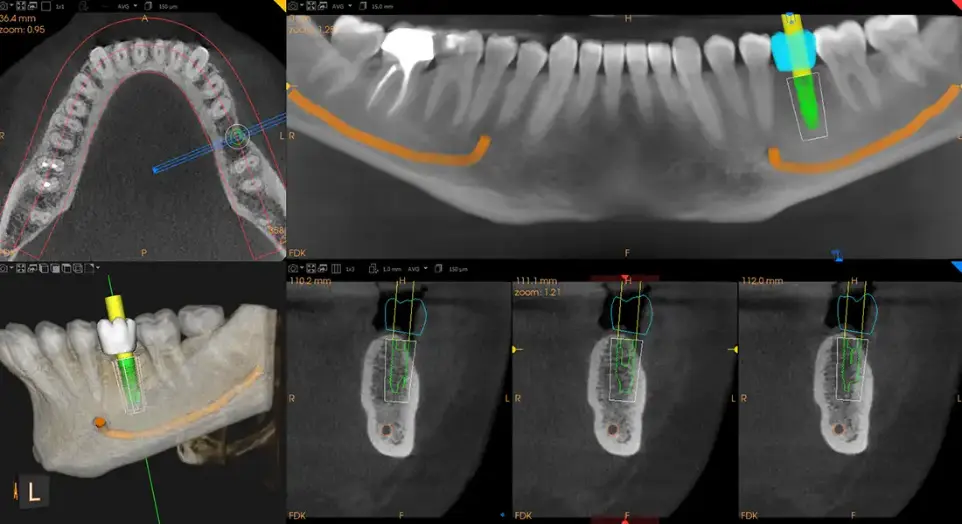

Personalized Treatment Planning

Each scan provides precise data for implants, root canals, TMJ therapy, or orthodontics, ensuring accuracy and comfort from day one.

Improved Comfort & Confidence: Because you’ll see what we see, you’ll better understand your treatment. And with high precision imaging, you can feel confident in the plan.